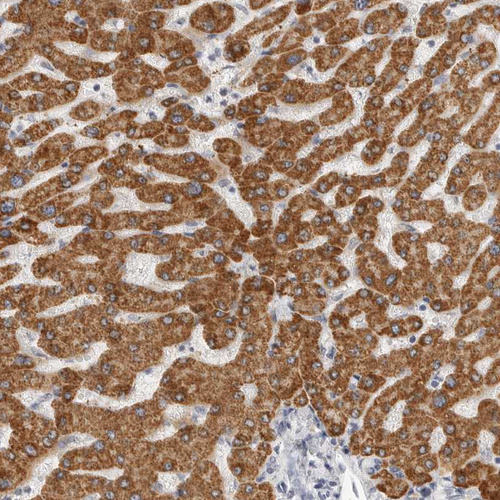

Immunohistochemistry analysis in human liver and cerebral cortex tissues using HPA027442 antibody. Corresponding HMGCS2 RNA-seq data are presented for the same tissues.